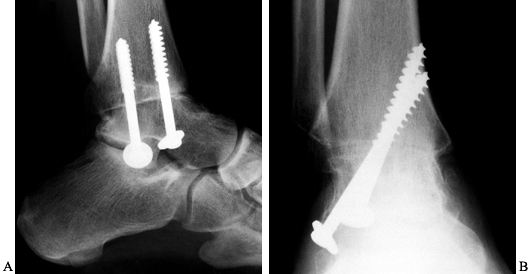

cast for another 6 weeks. As a general rule, the arthrodesis is solidly healed by 12 to 16 weeks (Fig. 115.2).

Figure 115.2. Radiographs demonstrating ankle arthrodesis utilizing the technique described in the text. On the AP view (B),

note that the screws engage the medial cortex to maximize interfragmentary compression. It is also important that the threads are past the fusion site. |